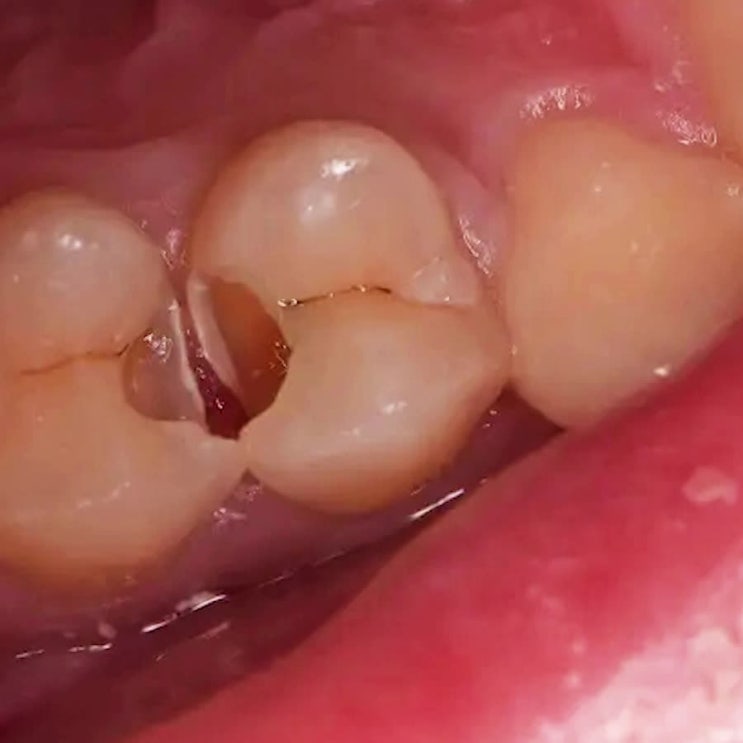

신제주충치치료 치아 사이로 많이 발견되는 검은 우식

치아가 서로 맞닿는 부위 치간 즉, 사이로 발생한 충치 평생을 써야 하는 영구치로 불리는 치아는 구강 내...